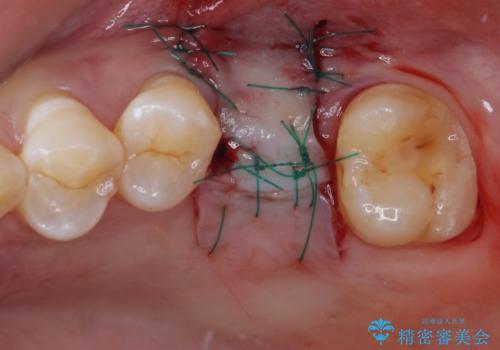

詰められた材料や壊死した組織を除去したところ、鮮明な破折線が認められたため、速やかに抜歯し、傷や骨の治癒を待って、サイナスリフトにより骨高さの低い部分にインプラント埋入を行いました。